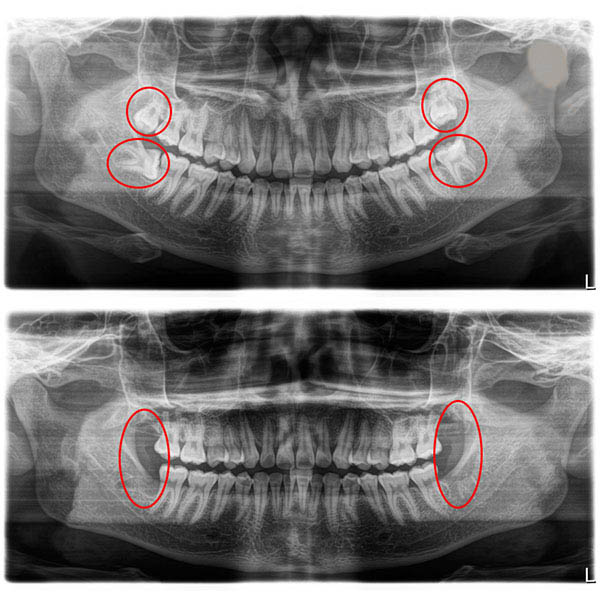

3.5 Chụp hình X-quang kiểm tra trước và sau nhổ răng

Việc chụp phim kiểm tra răng giúp xác định rõ hình dáng chân răng và xem có những răng ngầm, ổ răng ngầm nào không, để đưa ra hướng điều trị tốt nhất cho bệnh nhân. Sau khi nhổ răng một thời gian nhất định, bệnh nhân có thể được chỉ định chụp phim lần nữa để xác định không còn sót chân răng.